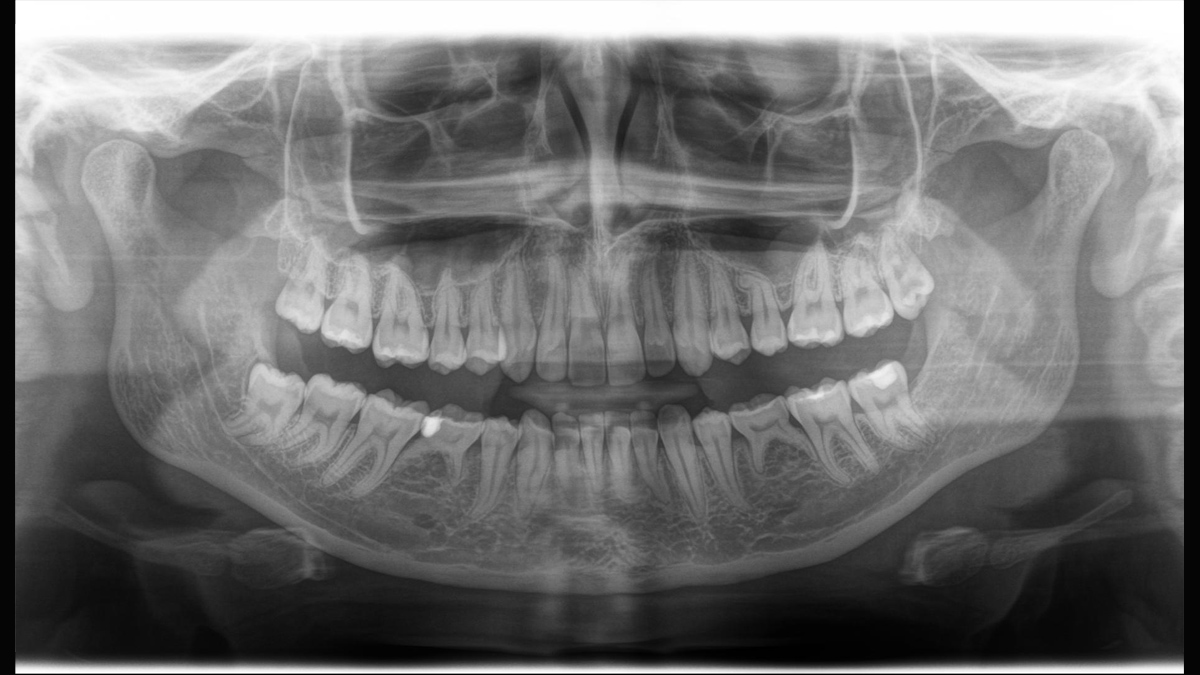

Aunque las radiografías 3D son cada vez más demandadas y existen un gran un número creciente de equipos en consultorios dentales, la imagen 2D sigue teniendo su lugar, en gran medida, debido a su radiación. Las mejoras realizadas en la calidad de imagen hace que las opciones disponibles en tecnología 2D están lejos de haberse agotado. Orthophos SL ha revolucionado la imagen 2D con la introducción del Sensor de Conversión Directa, la tecnología Sharp Layer y la SL interactiva. Experimente imágenes panorámicas como nunca antes.

Galería de muestra de imágenes panorámicas 2D